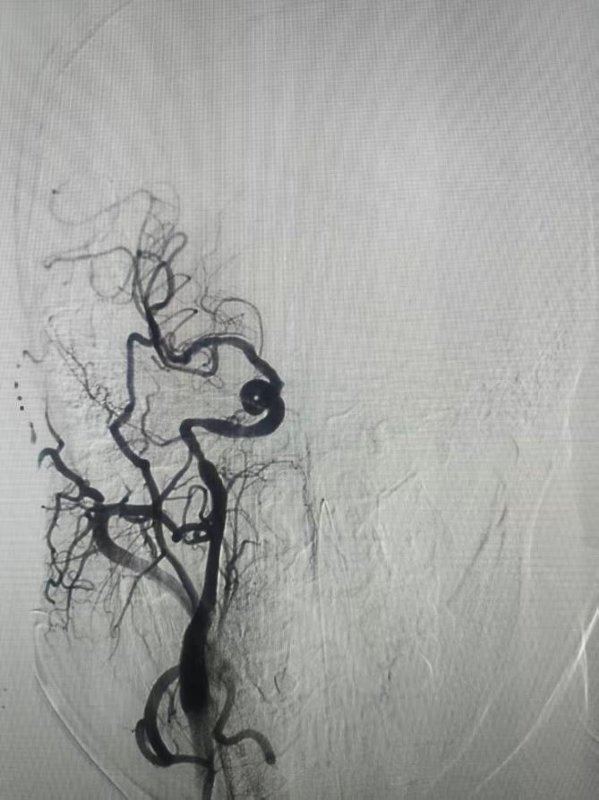

术后颈动脉成功开通

夹层远端继发血栓成功取出